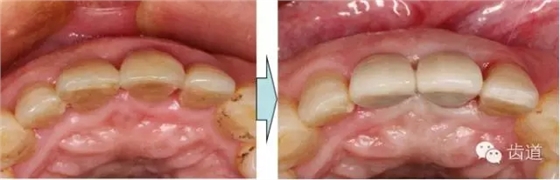

治療前后對(duì)比

戴牙半年后復(fù)查

戴牙一年前后對(duì)比